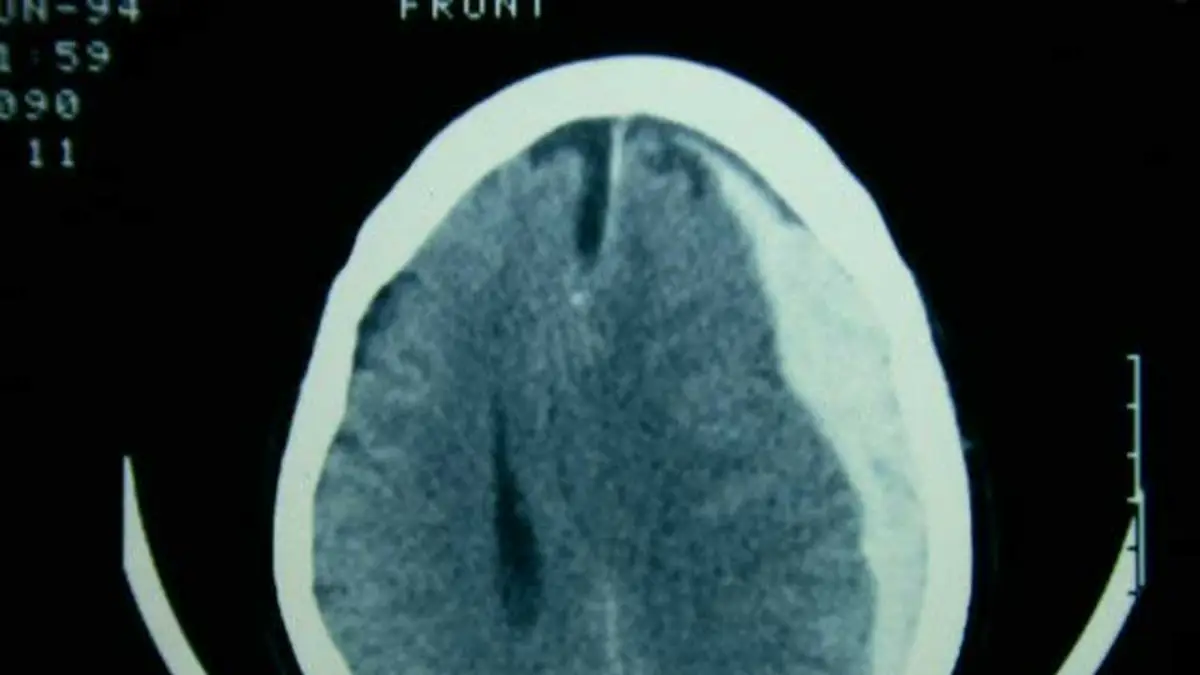

Sobre este punto el referente en la materia advirtió: “Ante cualquiera de estos signos, el procedimiento indicado es una Tomografía Computada (TAC) de cerebro, un estudio rápido que permite visualizar la acumulación de sangre”.